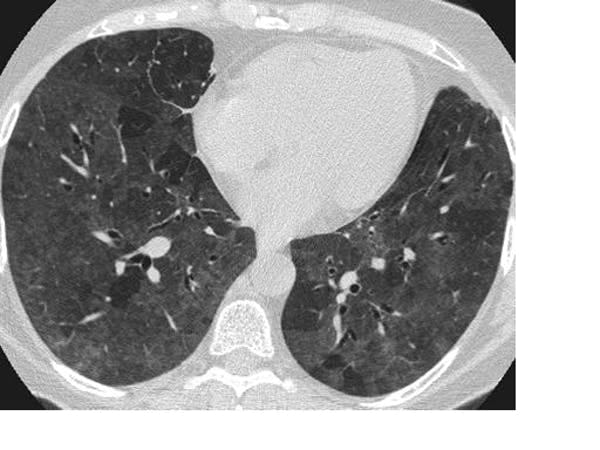

I quickly learned that many patients with advanced COVID-19 disease bore none of the hallmarks of severe respiratory illness until they suddenly collapsed and died. The science behind this early lesson is now emerging, with a study from Wuhan, China, describing pathological lung changes on CT scans of completely asymptomatic patients. Asymptomatic carriage is not uncommon in other virulent infections, such as MRSA and C diff, but what is striking with SARS-CoV-2 (the virus that causes COVID-19) is that it may be accompanied by underlying organ damage.

The researchers found lesions consistent with inflammation of the underlying lung tissue (ground-glass opacities and consolidation, to use the medical jargon), which are not specific to SARS-CoV-2 infection and may be seen in many other forms of lung disease. What remains a mystery is why, despite these changes, patients do not display typical symptoms of pneumonia, such as severe shortness of breath.